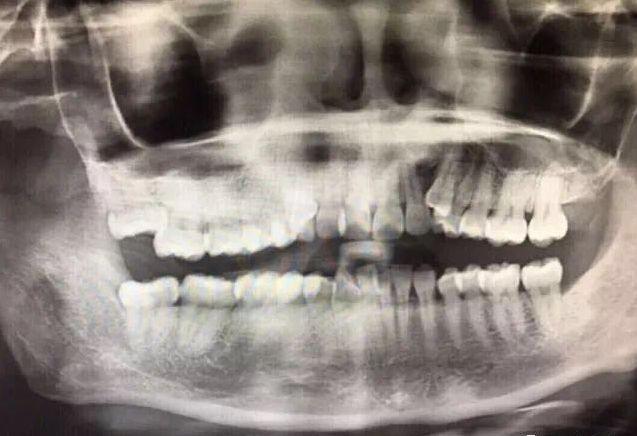

口腔CT檢查,牙齒問(wèn)題一目了然

62年,退休職員,牙齒缺失

趕在年前種好牙過(guò)年

“千萬(wàn)別小看缺牙,你以為不耽誤吃就沒事,其實(shí)還真不是那么回事。我就是個(gè)例子,自從掉了里面兩顆大牙,連脆香瓜都咬不動(dòng)。”

62歲的缺牙市民表示,自己缺牙這幾年,反復(fù)發(fā)作的牙周炎癥讓他備受煎熬,不僅吃東西咬不動(dòng)、嚼不爛,還影響了營(yíng)養(yǎng)吸收,體質(zhì)也變差。特別是講話漏音,還影響到自己的社交?!罢嫦M苤孬@一口好牙!”

報(bào)名本次活動(dòng)后,走出種牙室的第一時(shí)間,感覺輕松的爹爹特意對(duì)鏡頭豎起大拇指,表示對(duì)舒斯特博士種牙技術(shù)的贊賞:“牙椅都還沒躺熱,牙就種好了,而且不怎么痛!今年終于能好好吃年夜飯了!”